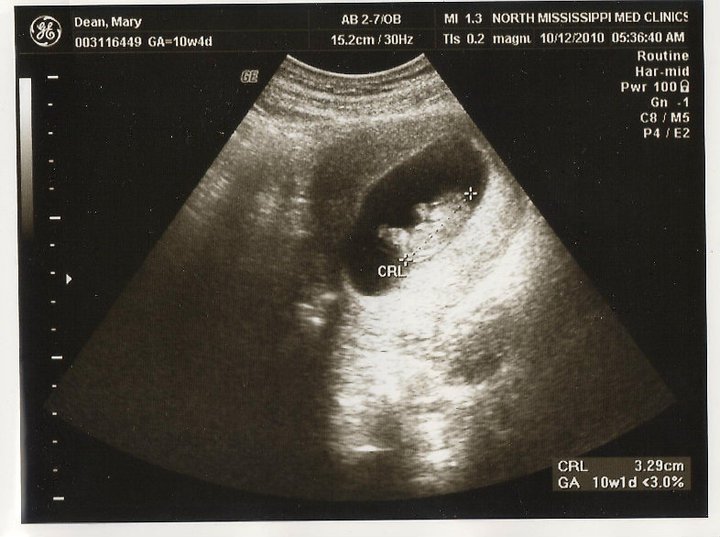

I've been growing up a storm, as you can see in the pictures below! Momma went to the doctor Monday and I weighed in at 1 lb. 14 oz. I'm in the 56th percentile for my gestational age (GA). Right now I'm still working on growing taller so one day I can be taller than Daddy, but I'm also putting on some fat to keep me warm once I arrive. I wonder how big I'll be.

|

| That's me at 10 weeks GA. You can see my tiny little foot! |